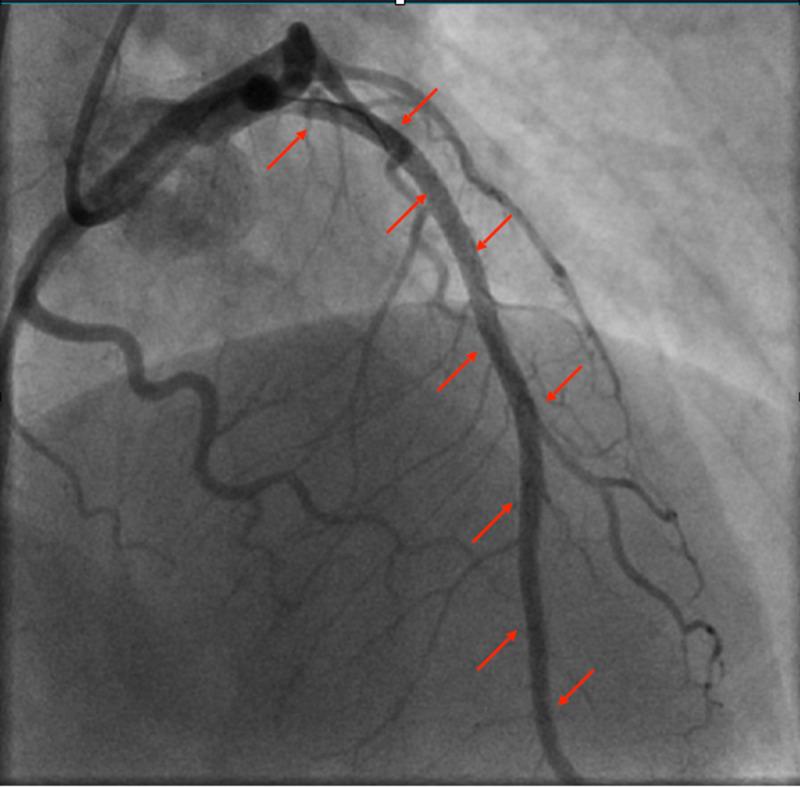

自发性冠状动脉夹层:年轻男性ST段抬高型心肌梗死的罕见病因。

Spontaneous Coronary Artery Dissection: An Unusual Cause of ST-Elevation Myocardial Infarction in Young Males.

Spontaneous coronary artery dissection (SCAD) is a non-traumatic, non-iatrogenic, and non-atherosclerotic coronary artery disorder that manifests clinically as an acute coronary syndrome (ACS), arrhythmia, or sudden cardiac death (SCD). It is a rare cause of ACS (1.7-4%) and SCD (0.5%), more commonly in women than men. It is rarely reported in males. We report a case of acute ST-elevation myocardial infarction (STEMI) due to SCAD in a 44-year-old healthy male.

摘要

自发性冠状动脉夹层(SCAD)是一种非创伤性、非医源性且非动脉粥样硬化性的冠状动脉疾病,临床上表现为急性冠状动脉综合征(ACS)、心律失常或心源性猝死(SCD)。它是ACS(1.7 - 4%)和SCD(0.5%)的罕见病因,女性比男性更常见。男性中鲜有报道。我们报告一例44岁健康男性因SCAD导致的急性ST段抬高型心肌梗死(STEMI)病例。